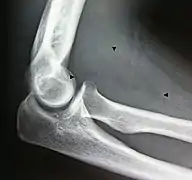

X-ray of a lipoma

X-ray showing lipoma